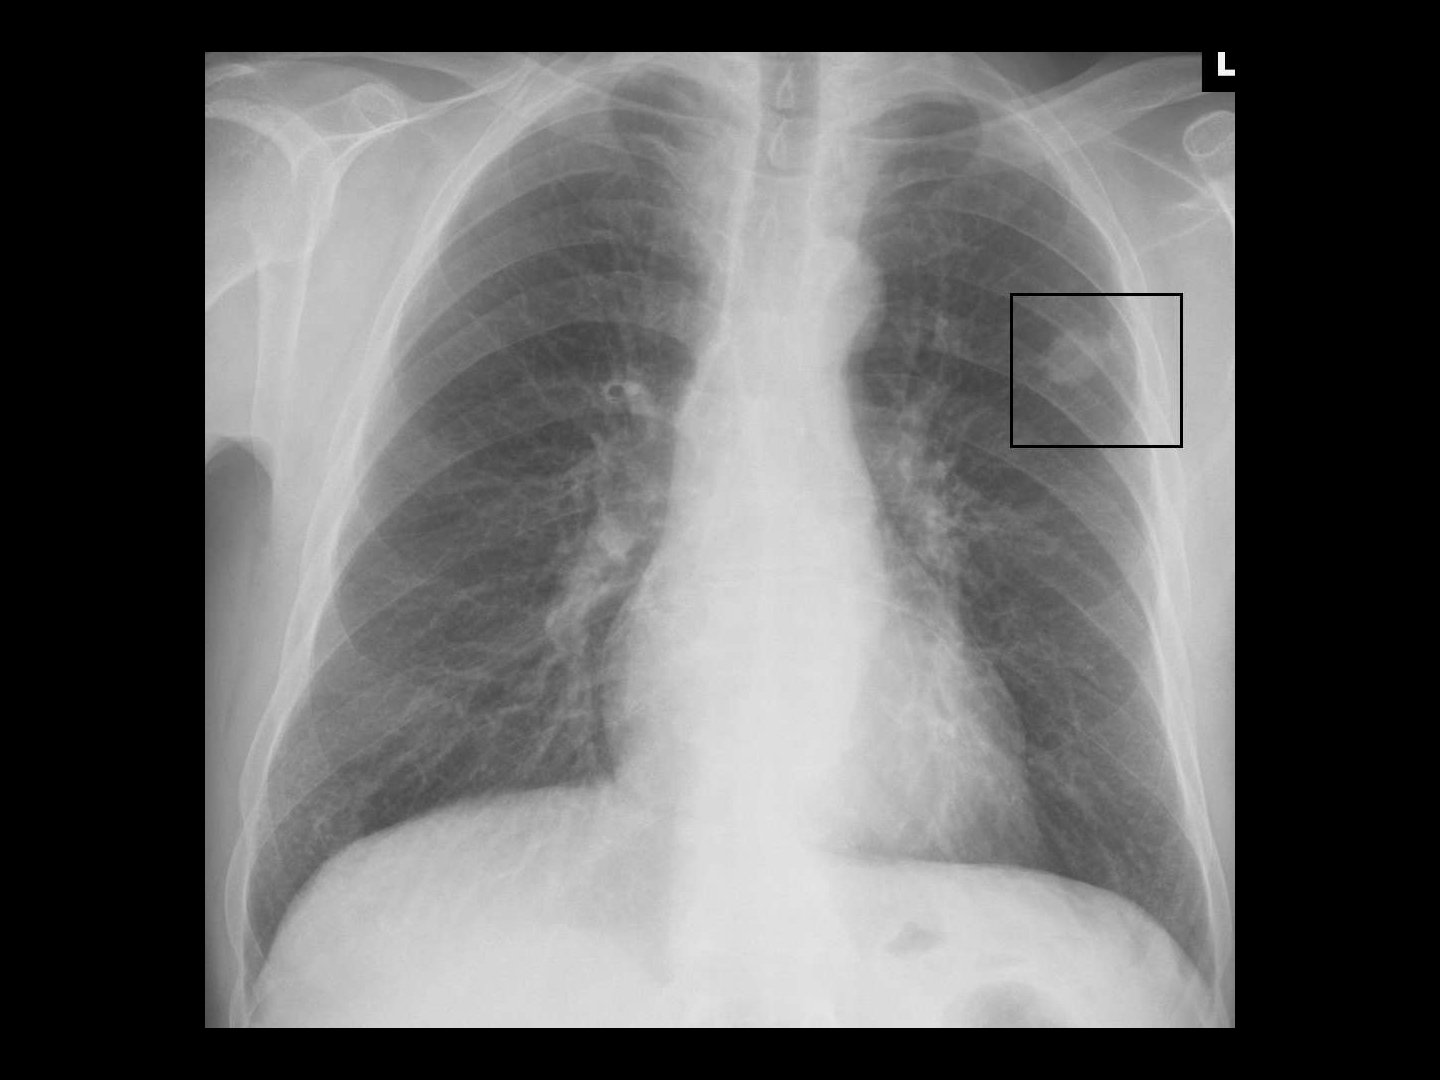

Diagnostik > Bildgebung

Rundherd: Wahrscheinlichkeit für Malignität ↗ bei > 40-Jährigen und Rauchern

Die Wahrscheinlichkeit, dass einem Lungenrundherd im Röntgen-Thx etwas Malignes zugrunde liegt, ist deutlich höher bei über 40-Jährigen und Rauchern.

Röntgen Rundherd → unscharfe Begrenzung

Gewisse Kriterien des Rundherdes deuten auf einen malignen Tumor hin.